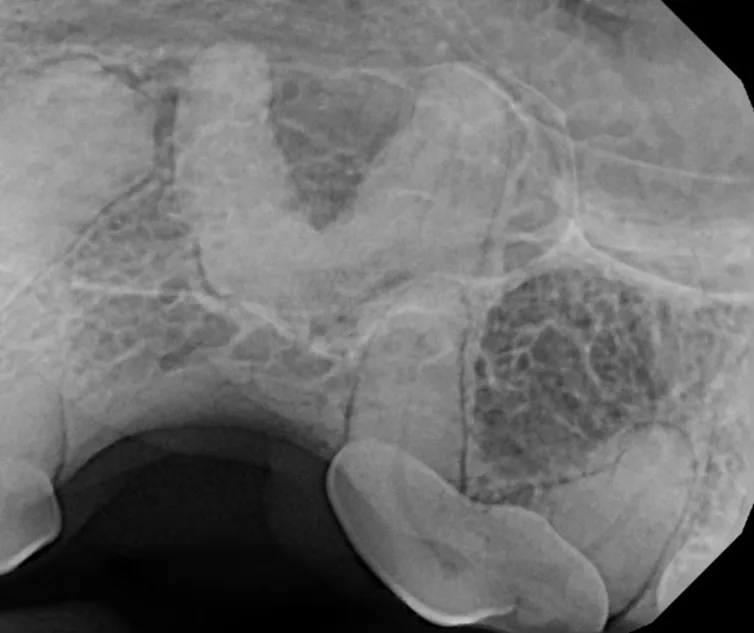

Oral tumors are very common in dogs and cats. Many of these tumors can be successfully removed with surgery. Benign tumors can be cured with surgery alone, and malignant tumors can be treated with surgery and some combination of radiation or chemotherapy. In many cases oral tumors cause a great degree of discomfort or are bleeding and need to be removed to allow your pet to be more comfortable.